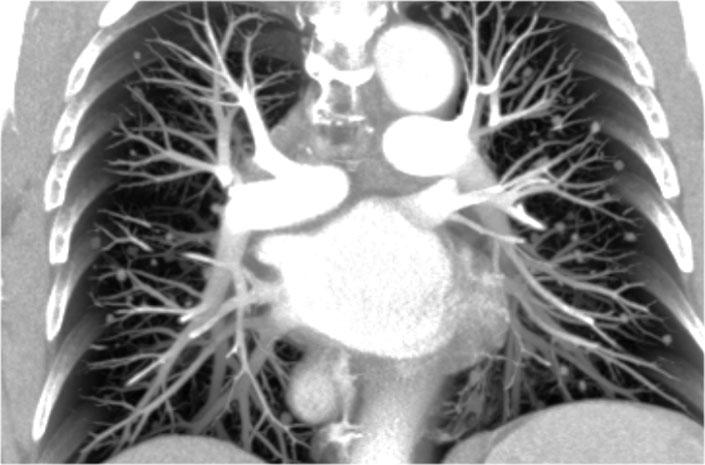

Bóng rốn phổi bình thường trên phim X-quang ngực có bản chất chủ yếu là mạch máu — bao gồm xấp xỉ 99% là các động mạch phổi và ở mức độ thấp hơn là các tĩnh mạch phổi (1).

Các cấu trúc mạch máu này có bờ viền rõ nét, nhẵn và thể hiện hình thái phân nhánh bình thường.

Hình ảnh

Tái tạo MIP dạng lát cắt dày theo mặt phẳng coronal tại mức rốn phổi.

Một đặc điểm giải phẫu quan trọng cần lưu ý là rốn phổi trái bình thường nằm cao hơn rốn phổi phải.

Mối tương quan này xuất phát từ đường đi của các động mạch phổi: động mạch phổi trái vòng cung qua phía trên phế quản gốc trái, trong khi động mạch phổi phải đi phía trước phế quản gốc phải — vốn thường nằm thấp hơn phế quản gốc trái.

Trong một số ít trường hợp, hai rốn phổi có thể nằm cùng mức, nhưng rốn phổi phải tuyệt đối không được nằm cao hơn rốn phổi trái.

Trong hình minh họa này, các động mạch phổi thùy dưới được tô màu xanh lam để biểu thị máu chưa được oxy hóa.

Các động mạch này có hướng đi thẳng đứng hơn so với các tĩnh mạch phổi, vốn chạy theo hướng nằm ngang hơn về phía nhĩ trái — nằm ở phía dưới so với mức các động mạch phổi chính.

Trên phim X-quang ngực tư thế nghiêng, cả động mạch và tĩnh mạch phổi đều có thể nhận diện được và không nên nhầm lẫn với hình ảnh hạch bạch huyết to. Đôi khi, các tĩnh mạch phổi có thể trông nổi bật hơn bình thường.

Động mạch phổi chính trái đi phía trên phế quản gốc trái và nằm cao hơn động mạch phổi phải — vốn đi phía trước phế quản gốc phải.

Các hình ảnh đính kèm là tái tạo CT lát cắt dày theo mặt phẳng sagittal của lồng ngực, giúp tăng cường khả năng hiển thị các cấu trúc rốn phổi.

Các động mạch phổi thùy dưới đi xuống từ rốn phổi theo hướng thẳng đứng.

Trên phim X-quang, các mạch máu này được gọi thông tục là “ngón út” do kích thước và hình dạng của chúng tương tự như ngón tay út (1).

Trên phim X-quang ngực tư thế thẳng (PA), “ngón út” của động mạch phổi thùy dưới phải có thể quan sát thấy ở khoảng 94% người bình thường, trong khi ở bên trái tỷ lệ này là khoảng 62% (1).